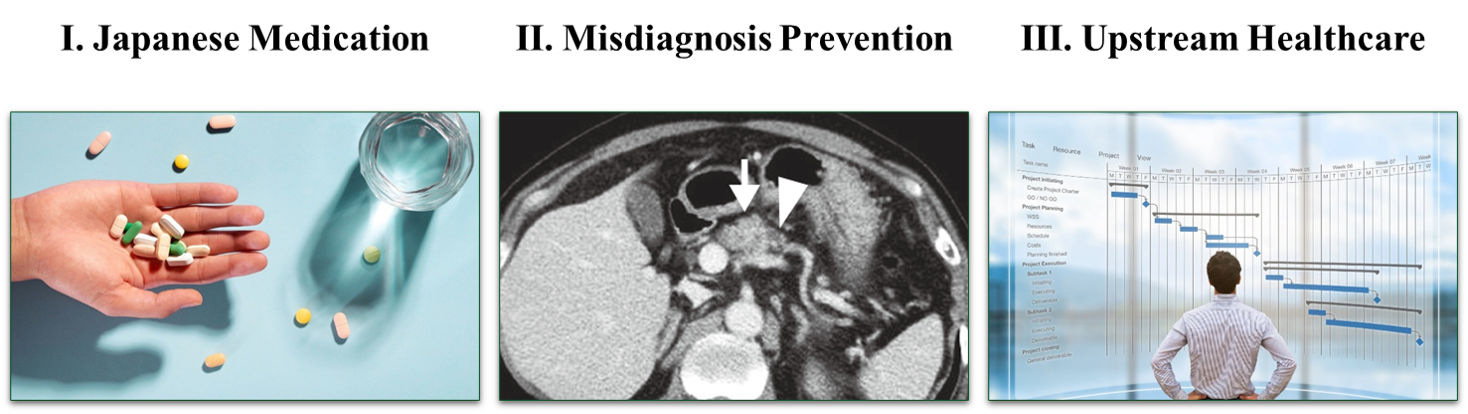

Japanese telehealth specializing in 3 areas

Ⅰ. Treatment of Lifestyle Diseases

Ⅱ. Treatment of Obesity

Ⅲ. Steps to use Japan Private Clinic services